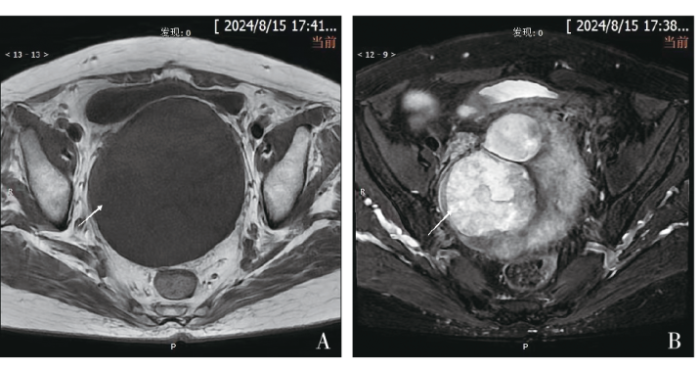

入院查体:外阴发育正常,阴道通畅,阴道残端愈合良好,盆腔内扪及肿物,大小约10 cm,活动度一般,无明显压痛。完善术前相关辅助检查,2024年8月15日查血常规示:平均血小板体积8.30 fL(参考值:9.2~12 fL),血小板分布宽度8.50 fL(参考值:9.6~15.2 fL),大型血小板比例11.4%(参考值:19.7%~42.4%)。D-二聚体1.11 mg/L(参考值:0~0.5 mg/L)。肝功能检查示:三酰甘油2.01 mmol/L(参考值:0~1.7 mmol/L),高密度脂蛋白胆固醇1.61 mmol/L(参考值:1.29~1.55 mmol/L),低密度脂蛋白胆固醇4.76 mmol/L(参考值:0~3.37 mmol/L),极低密度脂蛋白胆固醇0.91 mmol/L(参考值:0~0.78 mmol/L),脂蛋白a 0.35 g/L(参考值:0~0.3 g/L)。肿瘤标志物检查示:糖类抗原125(carbohydrate antigen 125,CA125)、CA19-9、癌胚抗原(carcinoembryonic antigen,CEA)、鳞状细胞癌抗原(squamous cell carcinoma antigen,SCCA)、甲胎蛋白(alpha-fetoprotein,AFP)及人附睾蛋白4(human epididymis protein 4,HE4)均未见异常。盆腔磁共振成像(magnetic resonance imaging,MRI)示:子宫及双侧附件切除术后;盆腔内见团块状混杂信号影,病灶边界清,边缘规整,大小约12.2 cm×10.4 cm×9.6 cm,T1加权成像(T1 weighted imaging,T1WI)以低、等信号为主,T2WI以高信号为主,弥散加权成像(diffusion weighted imaging,DWI)局部呈高信号(见图1)。2024年8月17日全腹CT示:盆腔巨大软组织肿块影,密度不均,局部可见结节状钙化影,增强扫描呈不均匀强化。考虑患者高龄,遂于2024年8月22日行超声引导下盆腔肿物穿刺活检术,术后病理回报:梭形细胞肉瘤。免疫组织化学检查示:结蛋白(Desmin,+),高分子量钙调蛋白结合蛋白(H-Caldesmon,-),CD34(-),CD117(-),Dog-1(-),细胞角蛋白(Cytokeratin,CK,-),S-100(-),抑制素-a(Inhibin-a,-),CD10(-),周期蛋白D1(Cyclin D1,-),B细胞淋巴瘤-2(B-cell lymphoma 2,Bcl-2,部分+),平滑肌肌动蛋白(smooth muscle actin,SMA,-),肾母细胞瘤基因1(Wilms tumor gene 1,WT1,-),间变性淋巴瘤激酶(anaplastic lymphoma kinase,ALK,-),成肌分化因子1(myogenic differentiation 1,MyoD1,部分+),Ki-67增殖指数(约3%+)。病理结合免疫组织化学结果,考虑为梭形细胞横纹肌肉瘤。

图1

DAA发病率较低,临床误诊率极高,因此,特殊的影像学特征对于该病的诊断至关重要。DAA在超声中仅表现为低回声包块,在CT中表现多样,但缺乏特异性,因此其通常只能作为初步筛查手段[6]。而在MRI中DAA可以呈现出清晰的边缘和特征性的漩涡状或分层结构,这有助于与其他肿瘤相鉴别,因此影像学检查中MRI对DAA最具有诊断价值。DAA在MRI图像中,T1WI以低、等信号为主,T2WI表现为高信号或较高信号,这可能与肿瘤中富含大量胶原纤维和血管结构有关[1,3]。既往研究表明,由于DAA基质疏松,且富含黏液,其在DWI序列中也有特殊表现,即肿块在DWI序列中呈现明显的高信号[7]。本例患者术前进行的妇科超声及盆腔CT检查均未发现有意义的阳性征象,而在盆腔MRI检查中呈现出团片状长T1、长或短T2信号,DWI局部呈高信号,提示可能为DAA。更为重要的是,通过盆腔MRI的影像学评估,不仅明确了病灶的具体大小和浸润范围,还提供了病灶与周围组织的关系,为拟定手术方案、手术方式提供指导。